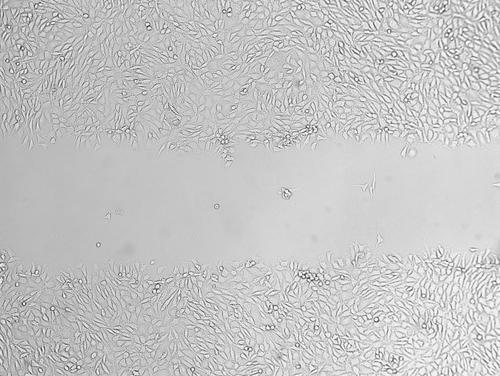

細(xì)胞劃痕實(shí)驗(yàn)|專注醫(yī)學(xué)科研外包

細(xì)胞劃痕是一種簡(jiǎn)單易行的檢測(cè)細(xì)胞運(yùn)動(dòng)的方法,實(shí)驗(yàn)成本低,可以用來(lái)檢測(cè)貼壁生長(zhǎng)腫瘤細(xì)胞的侵襲轉(zhuǎn)移能力。

細(xì)胞劃痕實(shí)驗(yàn)服務(wù)